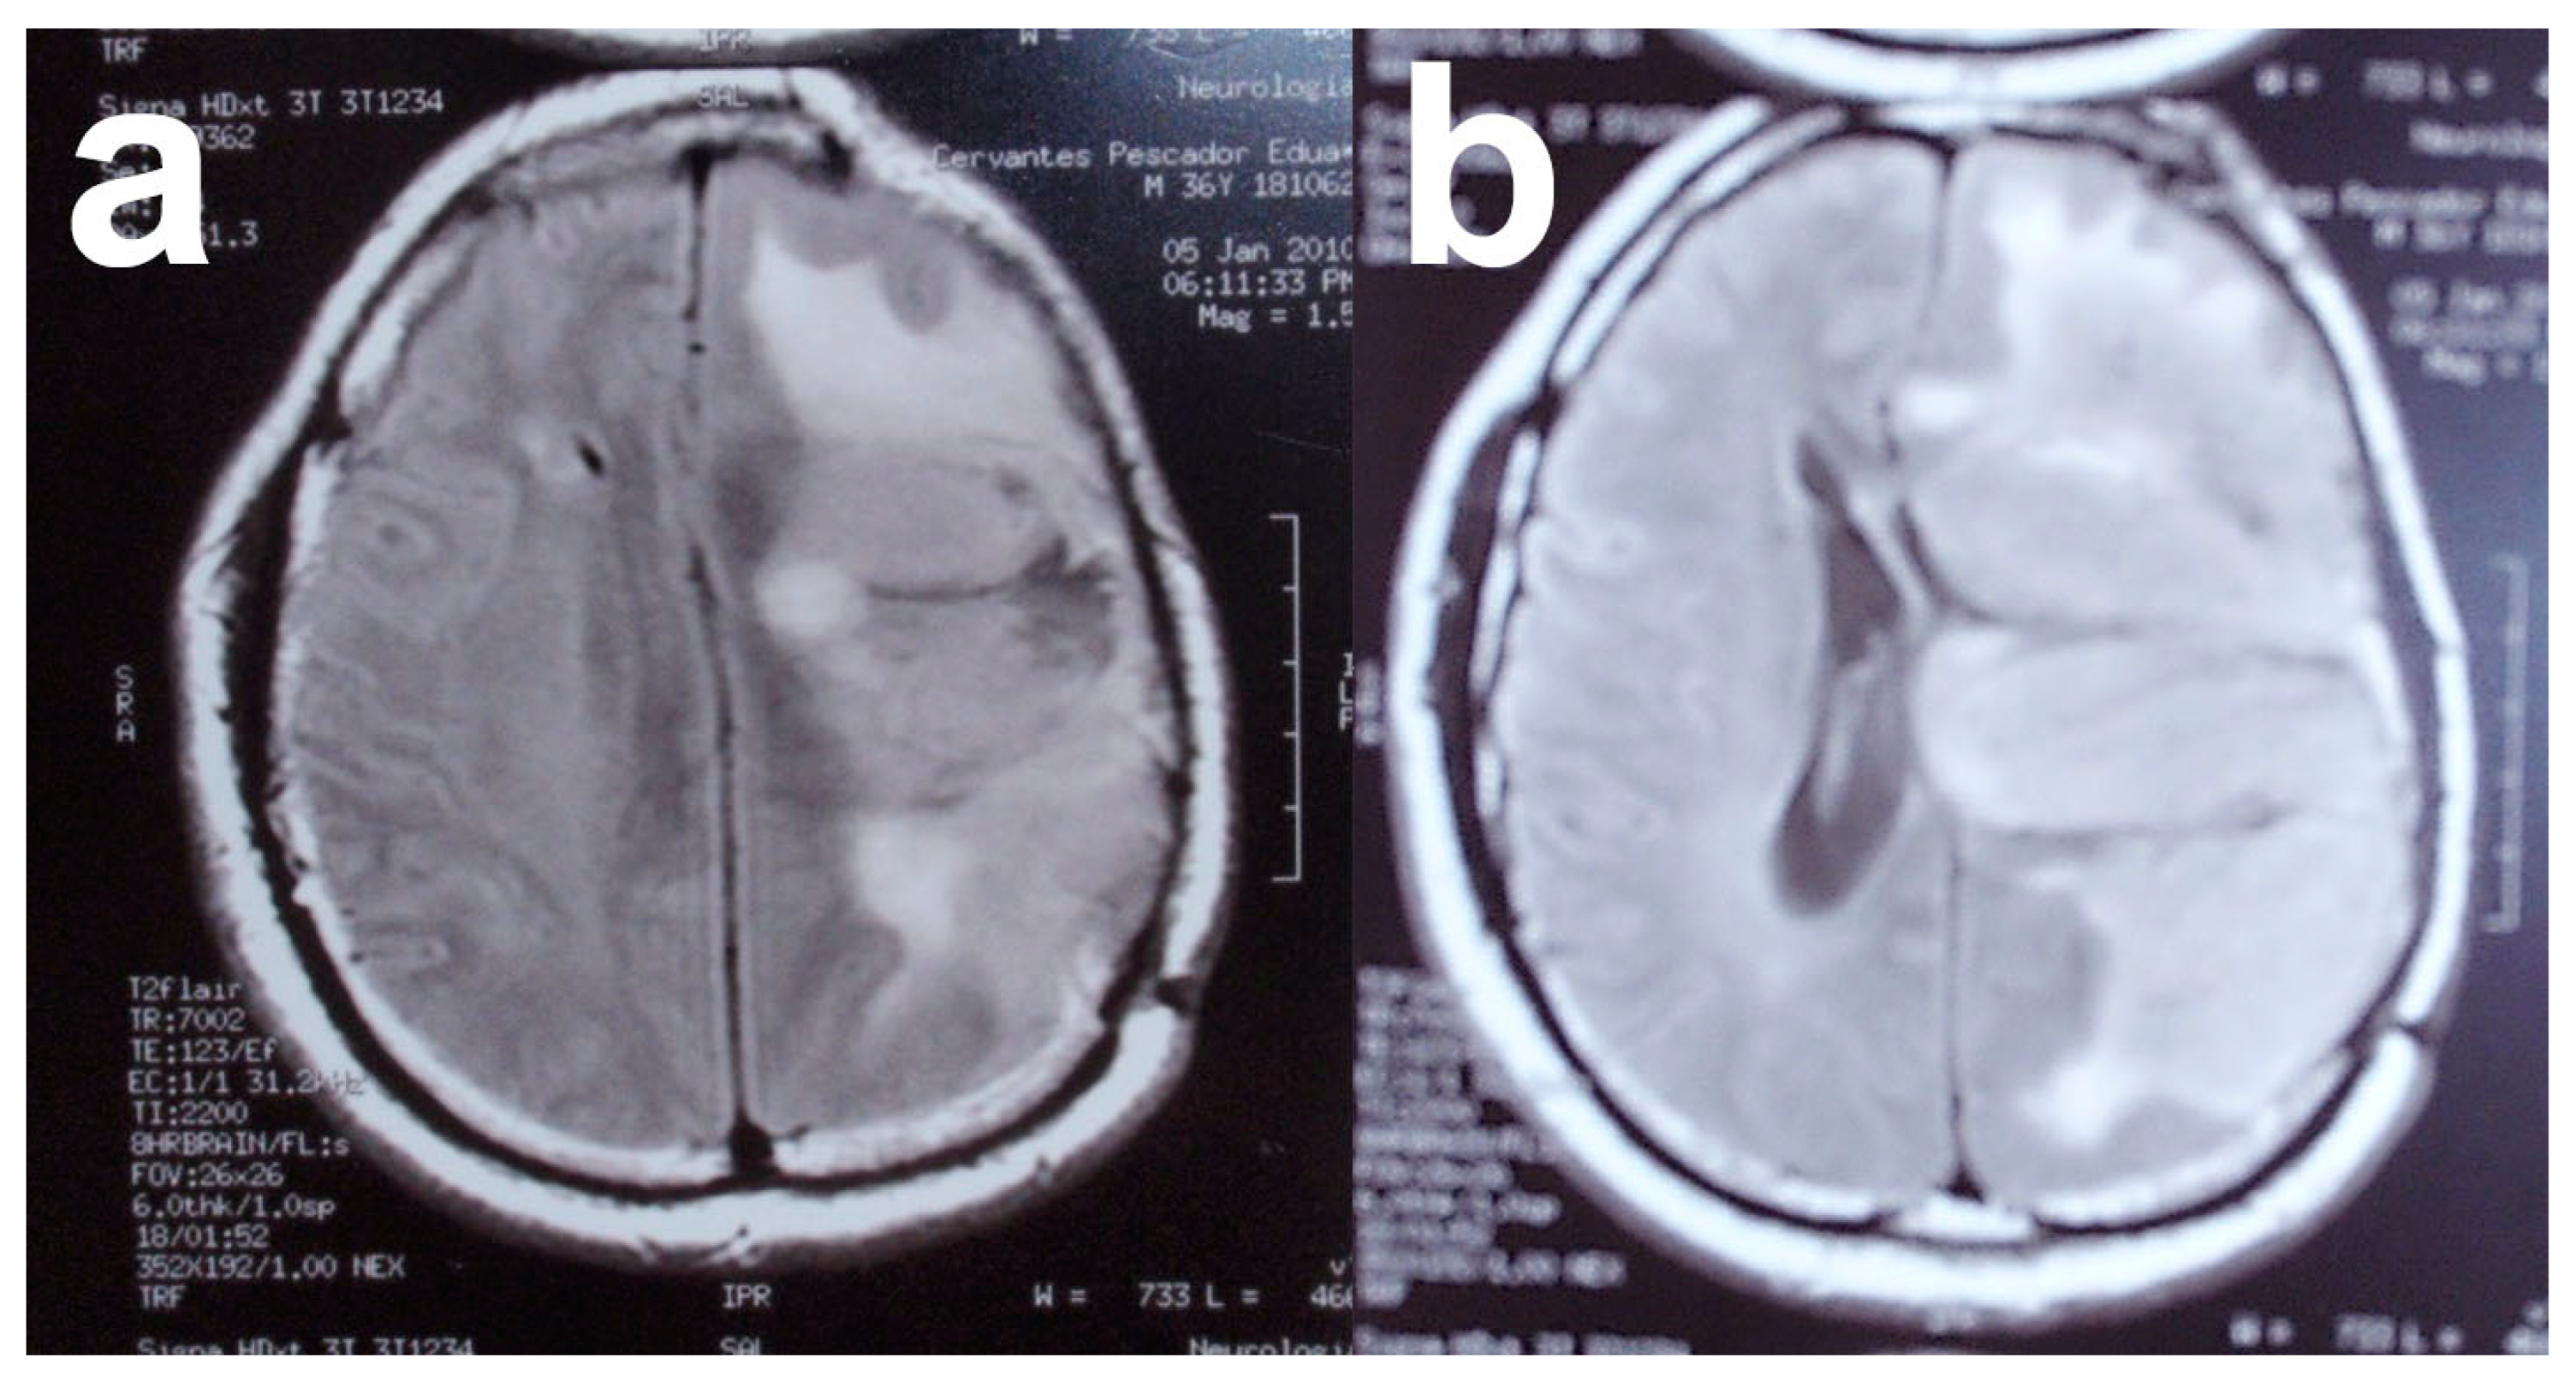

The typical MRI appearance of glioblastoma is a mass lesion, often iso- to hyperattenuating (bright) compared with normal gray matter, with surrounding hypoattenuation by infiltrating tumor and vasogenic edema [116]. Classically, contrast-enhanced MRI reveals a centrally necrotic enhancing mass. Since vascular proliferation is a hallmark of glioblastoma, intra-tumoral hemorrhage is common and can be visualized on MRI, although it is more frequently identified as microbleeds on susceptibility-weighted imaging (SWI) MRI [117]. Calcification is uncommon in glioblastoma, but can occasionally be seen [118]. On MRI, almost all glioblastomas are gadolinium-enhanced [119]. In the case of this patient, MRI revealed the presence of a tumor in the right hemisphere (Figure 6).

Figure 6.

(a,b) Magnetic resonance images of patient with solid glioblastoma multiforme tumor. Images from personal archive.